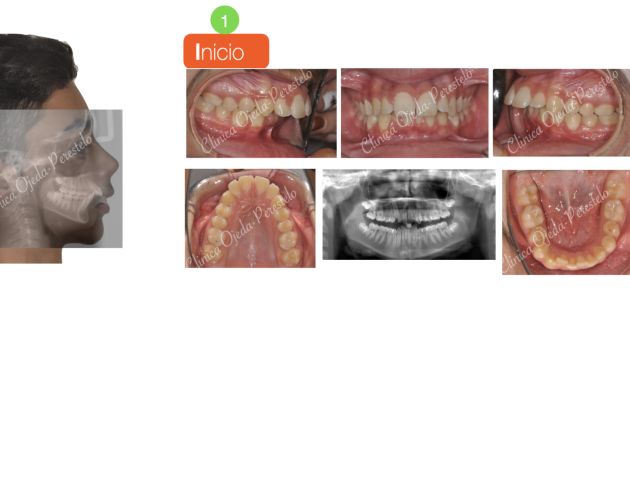

Apiñamiento severo con molares con mal pronóstico Casos de Éxito - Adultos